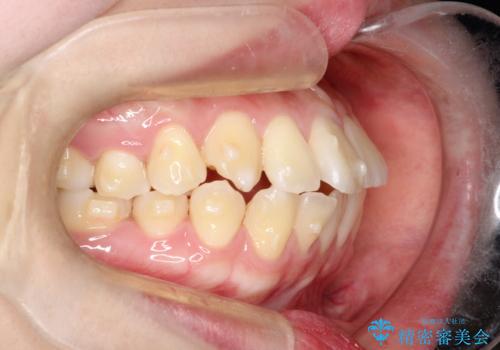

【インビザライン】歯を抜かずにできるだけ前歯を下げたい

- 前歯の前突を主訴に来院されました。

インビザライン を用いて、歯並びの改善を行うことができました。